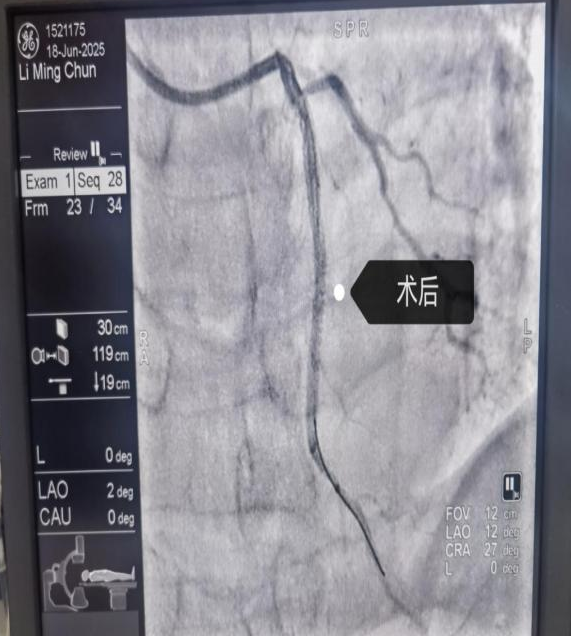

近期科室开展手术患者影像

支架植入术是在冠状动脉造影基础上进行的微创介入治疗,通过病变部位球囊扩张和药物洗脱支架植入,撑开狭窄或闭塞的冠状动脉,恢复血流畅通,是治疗严重冠心病(尤其是急性心梗)的关键技术。

近期重庆三峡医专附属中医院心血管病科连续开展多例冠状动脉造影术+支架植入术,该类型手术的常规开展,标志着医院心血管病科从传统中西医结合内科治疗心血管疾病进入了中西医结合+介入手术治疗的新阶段。